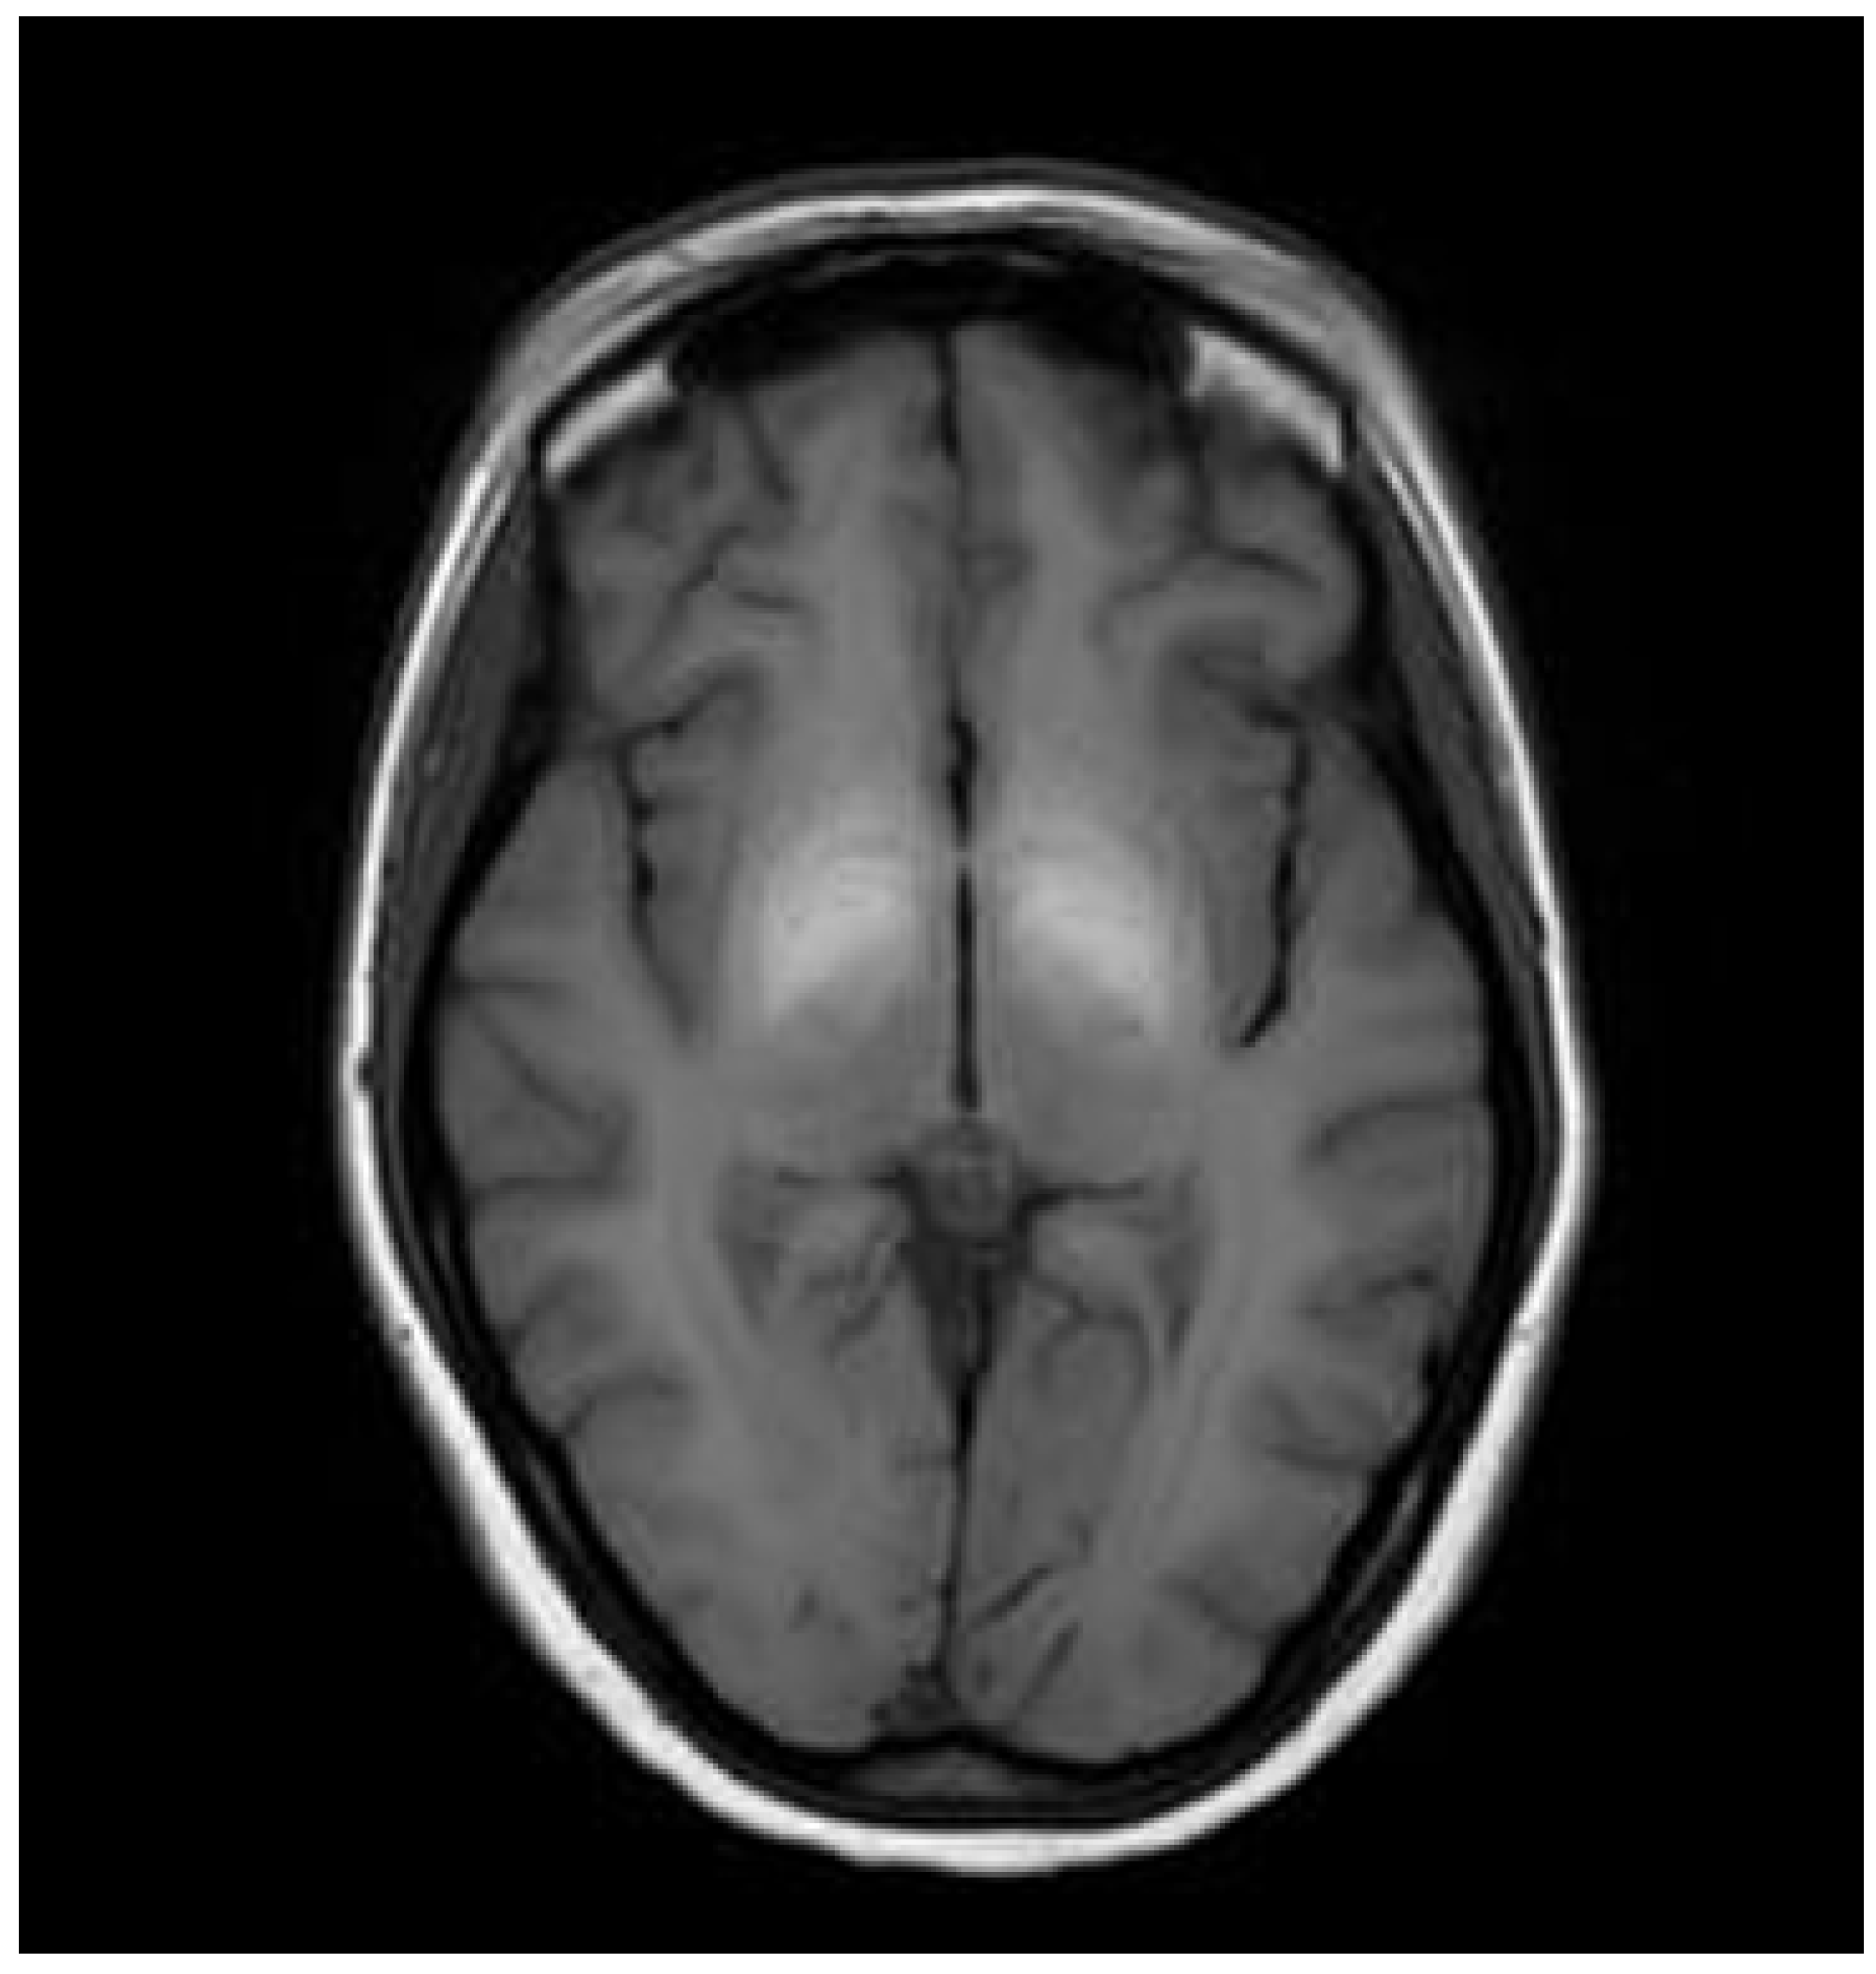

In the course of Wilson’s disease (WD), alongside lesions predominantly located in the basal ganglia, mesencephalon, and pons, anatomopathological studies have consistently described the WD brain as soft, exhibiting loss of both deep and superficial white matter, slight atrophy, and enlarged ventricles [54,55,56]. Since the advent of neuroimaging studies in WD (using brain CT or MRI), brain atrophy has been documented with cortical or ventricular widening observed in nearly 40% of patients, particularly those with neurological manifestations (204 patients with WD) [22]. Initially, radiologists subjectively assessed atrophy (presence/absence) [49,56,57,58,59,60] (Figure 6A,B).

Cortical atrophy (A) and central atrophy with widening of the third ventricle (B) in T1-weighted sequences (own materials of the neurology department).

In subsequent studies, traditional linear brain measurement indices, such as the Huckman number, are defined as the sum of the maximum distance between the anterior horns and the minimum distance between the bicaudate nuclei. This parameter is useful for evaluating ventricular enlargement, particularly the diameter of the anterior ventricular horn, third ventricle width, ventricular index, and sulcus width, which were utilized to quantify brain atrophy, particularly in patients with neurological manifestations of WD [57,58]. As the analysis of brain atrophy evolved with the introduction of objective software tools similar to those used in multiple sclerosis (which are even used as secondary endpoints in clinical trials), studies began employing software like SIENAX, FreeSurfer (2.6/FSL 6.0), (and voxel-based morphometry to assess brain parenchyma in WD. One of the pioneering studies utilizing SIENAX was conducted by Smolinski et al., who examined 48 treatment-naïve WD patients and observed correlations between neurological deficits, functional impairment (as measured by Unified Wilson’s Disease Rating Score (UWDRS)—clinical scale for patients with WD describing the severity of neurological symptoms and ambulation), and total brain volume, as well as volumes of white and gray matter [59]. The authors further noted associations between ‘toxic copper’ (NCC) levels and reduced brain volumes. In a subsequent longitudinal investigation, the authors analyzed baseline and follow-up brain MRIs of WD patients over a period exceeding 12 months (fifty-seven patients with WD; thirty-six neurological, seventeen hepatic, and four presymptomatic). They found that the annualized rate of brain atrophy, defined as the longitudinal percentage change in ventricular volume (PVVC), was notably higher in neurological WD patients (median 5.4%) compared to non-neurological WD patients (0.5%, similar to healthy populations). Furthermore, the extent of atrophy varied depending on the neurological subtype (e.g., more severe forms like dystonia exhibited 14%, parkinsonian 7.9%, and tremor 4.3%) and disease progression—patients experiencing neurological deterioration showed rates as high as 16.7% [56].

More comprehensive whole-brain analyses employing deformation and surface-based morphometry were conducted by Dusek et al. in 2021 [49] (29 patients with WD and 26 controls), revealing atrophy affecting deep gray matter nuclei, brainstem, internal capsule, motor cortex, and corticospinal cortex in WD patients. These findings were corroborated by voxel-based morphometry and region-of-interest volumetric analyses performed by Shribman et al. [55], who also observed reduced gray matter volumes in basal ganglia, thalamus, brainstem, cerebellum, anterior insula, and orbitofrontal cortex among neurological WD patients compared to hepatic WD patients (40 patients with WD, 23 neurological, and 17 hepatic). The severity of neurological deficits, as previously noted, correlated with the extent of neurological symptoms assessed using UWDRS.